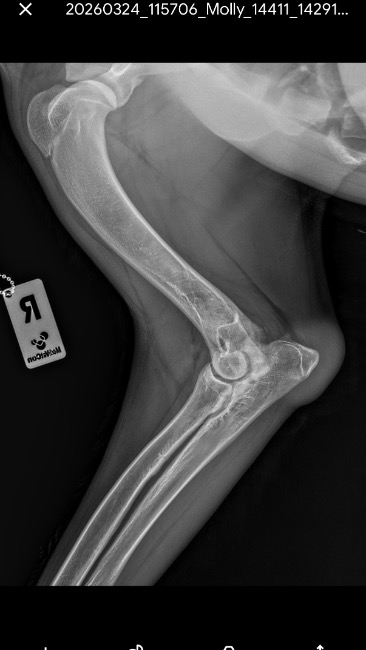

Molly regularnie uczęszczała na fizjoterapię bo lekarze dawali jej szansę „ a może jeszcze się trochę zrośnie„. Po kolejnych tygodniach/ miesiącach walki dysplazja zaczęła być widoczna gołym okiem - łopatka która „wypadała „ , wykrzywione przednie łapki - szczególnie w stawach łokciowych, jeszcze mocniejsze „rzucanie” podczas gdy pies chciał się położyć, spacery które i tak wedle zaleceń były bardzo krótkie skróciły się jeszcze bardziej, widać było że aktywnosci nawet te najprostsze sprawiały jej duży ból … oczywiście Molly cały czas przyjmowała leki i suplementację aby się tak nie męczyła..

Z góry ogromnie dziękujemy nawet za najmniejsze wpłaty oraz udostępnienia ;) zalaczam również dokumentacje medyczna